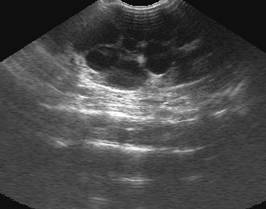

Прості кисти нирок, як правило, є

випадковими знахідками. Вони виявляються при ультразвуковому обстеженні як

поодинокі, круглі, ехонегативні утворення з дистальним підсиленням, що

викликане підвищеною звуковою трансмісією. Складні кисти можуть мати ехогенні

перетинки або уламки.

Рис. 2. Проста киста правої нирки

(стрілка) у кота 2 років